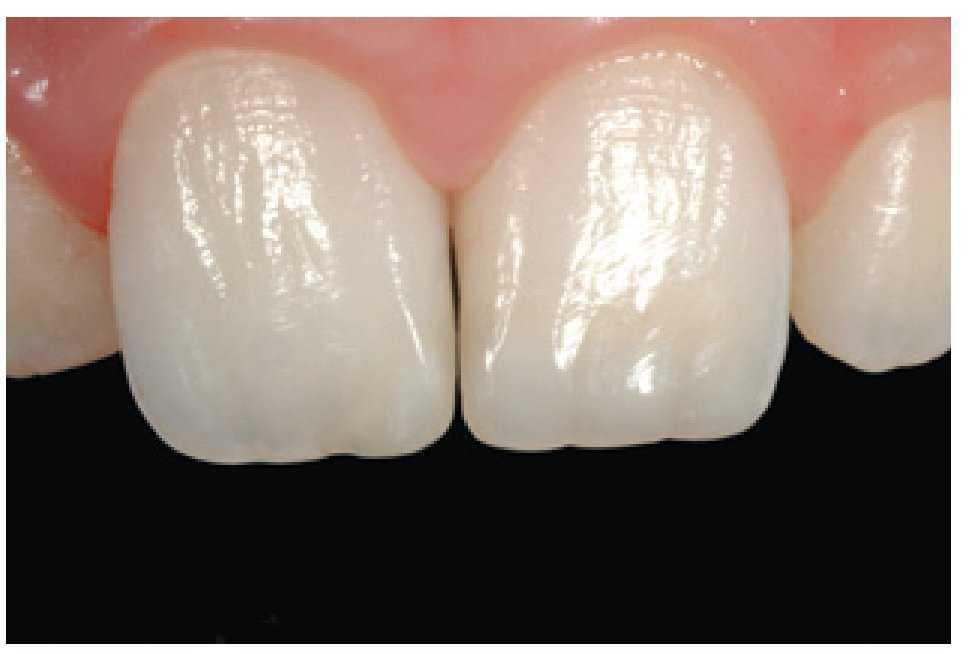

El pulido final es fundamental para el éxito estético de las restauraciones, ya que una superficie brillante y lisa reduce el acúmulo de placa y previene la decoloración de los dientes (Shiny System, Micerium). Al final, la restauración pulida presentaba una superficie muy similar a la del diente natural (figuras 49 y 50). No obstante, este nivel de resultado clínico obtenido con una técnica directa sólo es posible con un manejo correcto de la forma y la reconstrucción. Estos parámetros deben ser determinados antes de instaurar los procedimientos clínicos (figuras 51 y 52).

Figura 49 Vista de las restauraciones y los elementos rehidratados después de 72 horas.

Figura 50 Buena integración estética de las restauraciones y salud de los tejidos periodontales 30 días después del tratamiento.

Figura 52 Revisión a los dos años.